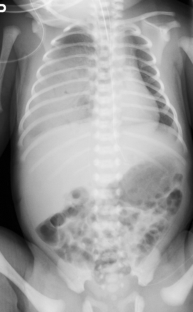

Congenital pulmonary airway malformation (CPAM) is classified into pathologically different types. These types are sometimes distinguishable by fetal lung MRI and are usually observed as higher-signal lesions on T2-weighted images than normal lung. We describe a case of unusual CPAM resembling neoplasms, with a lower signal than is found in normal lung. Histopathology showed a large number of mucogenic cells but found no evidence that could explain this feature on fetal MRI. An unusual low-signal mass associated with a pulmonary cyst in fetal lung on MRI may suggest an unusual type 1 CPAM.

Fig. 2